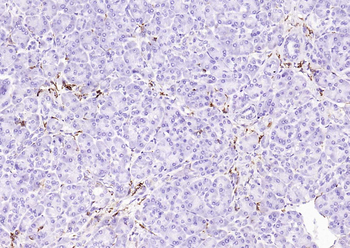

50 μl, 100 μl - KLF4 Recombinant Rabbit Monoclonal Antibody [orb608075]Featured

FC, ICC, IF, IHC-Fr, IHC-P, WB

Human, Mouse, Rat

Rat

Rabbit

Recombinant

Unconjugated

200 μl, 50 μl, 100 μl - Featured